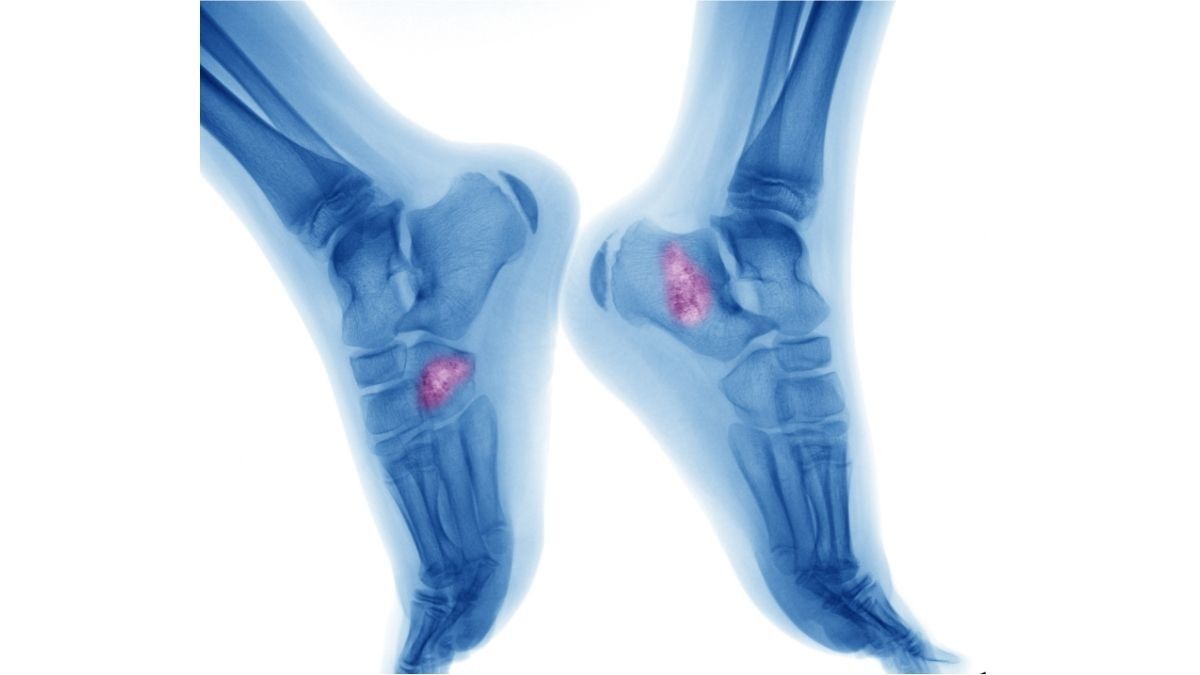

Pasien kanker tulang osteosarkoma yang tengah menjalani terapi pengobatan cenderung tidak memiliki nafsu makan.